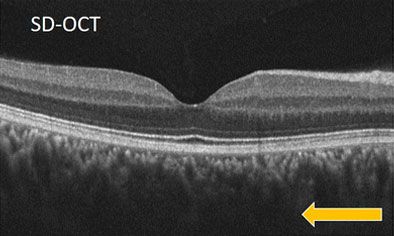

При SD-OCT хориоидея визуализируется слабо — размыты границы, особенно в глубоких слоях. При SS-OCT сосудистая оболочка чётко прослеживается по всей толщине до склеры благодаря высокой проникающей способности инфракрасного лазера.